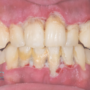

Una encía sana debe ser color rosa pálido. Estos son algunos de los síntomas de la periodontitis

- Encías enrojecidas o moradas

- Encías sensibles al tacto

- Encías que sangran al cepillarse los dientes

- Escupir sangre al enjuagarse la boca

- Dolor al masticar

- Halitosis o mal aliento

- Dientes flojos o perdida de los mismos